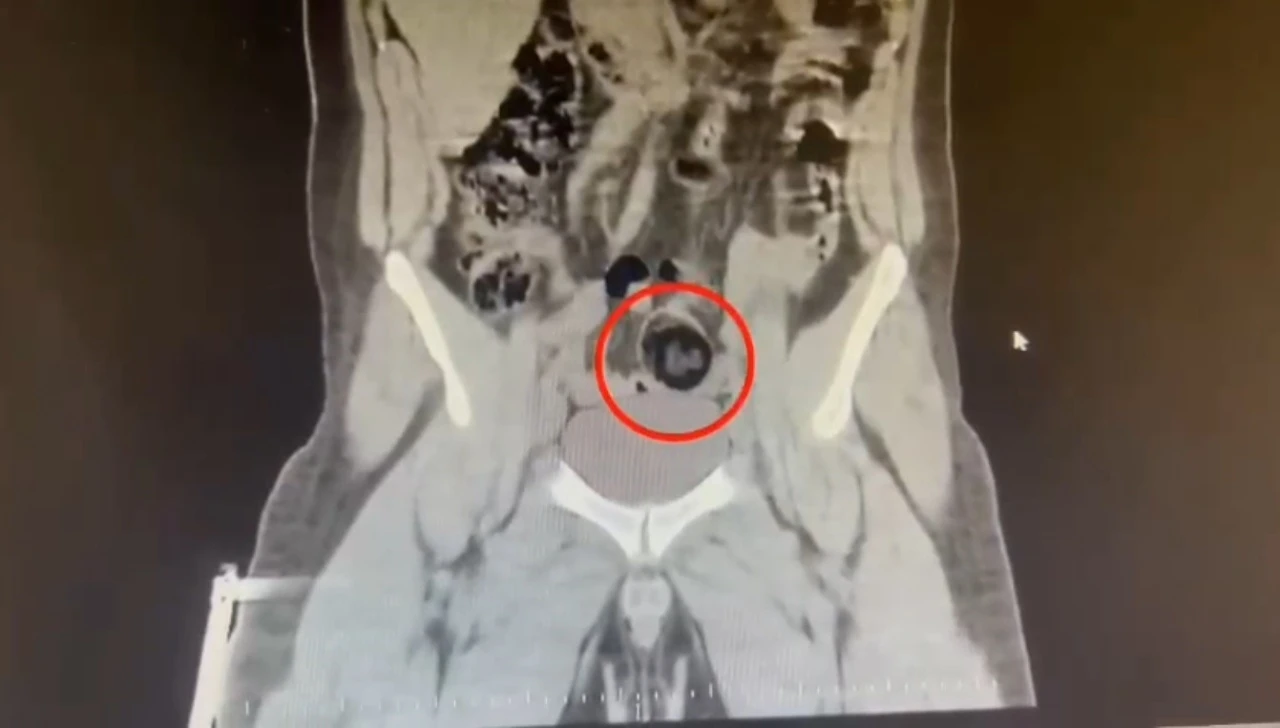

Kars Emniyet Müdürlüğü Narkotik Suçlarla Mücadele Şube Müdürlüğünce, savcılık koordinesinde kent merkezinde uluslararası uyuşturucu madde ticareti yapan kurye şahıslara yönelik operasyon düzenlendi. Bu kapsamda narkotik ekiplerince durdurulan yolcu otobüsünde İranlı kurye yakalanarak gözaltına alındı. Şüpheli hareketler sergilen kurye götürüldüğü hastanede yapılan iç beden muayenesinde makatında cisim olduğu anlaşıldı. Kuryenin makatındaki 105,98 gram metamfetamin gerçekleştirilen cerrahi müdahaleyle çıkarıldı. Gözaltına alınarak emniyete getirilen kurye, çıkarıldığı mahkemece "TCK-188 uyuşturucu veya uyarıcı madde imal ve ticareti yapmak" suçundan tutuklanarak cezaevine gönderildi.